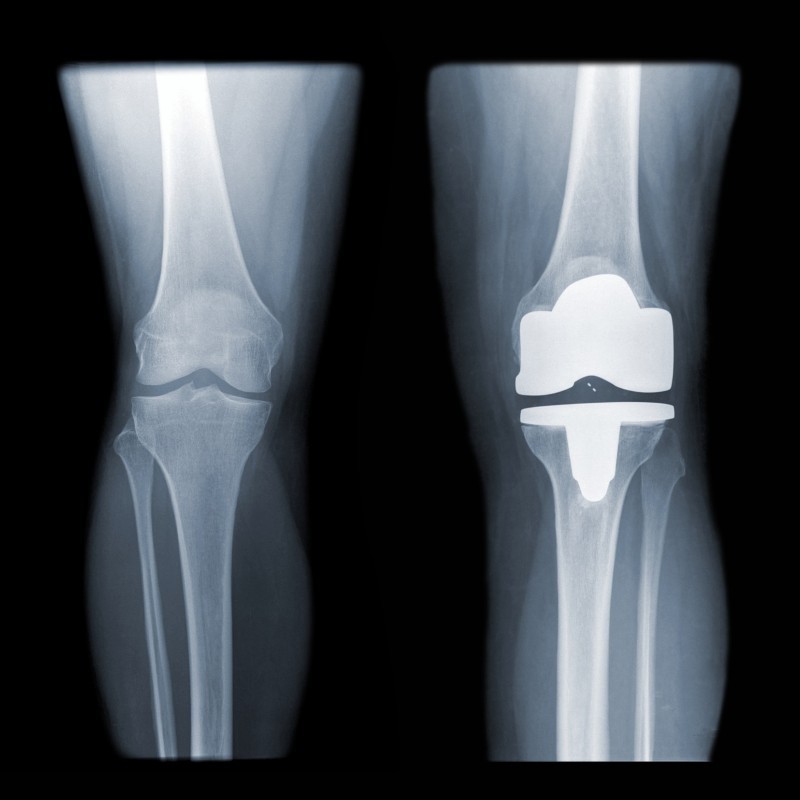

Wanneer u bij toenemende slijtage (artrose) van het gewrichtskraakbeen ook meer pijnklachten ervaart, kan het plaatsen van een prothese (kunstgewricht) een oplossing zijn. Bij de chirurgische ingreep wordt het beschadigde kniegewricht vervangen door een kunstgewricht.

Zowel het botoppervlak van het dijbeendeel en het scheenbeendeel kunnen dan vervangen worden door een combinatie van metalen, kunststof of soms keramische componenten. Dit wordt vaak gedaan bij mensen die lijden aan ernstige artritis of andere aandoeningen die pijn en bewegingsbeperkingen veroorzaken in de knie. Afhankelijk van verschillende factoren zoals de botkwaliteit, leeftijd of een eerdere prothese zal de orthopedisch chirurg kijken welke prothese en operatietechniek het meest geschikt is

De prothese bestaat meestal uit:

• Metalen dijbeendeel

• Metalen scheenbeendeel

• Kunststof lagers tussen scheenbeendeel en dijbeendeel

Knie met halve protheseKnie met totale prothese